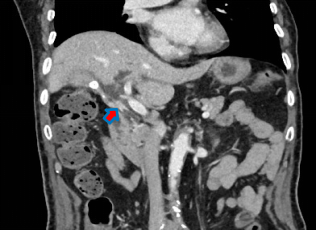

据患者女儿反映,范先生刚于今年 2 月做完肠癌手术,发现全身发黄症状后第一时间做了 CT 检查,提示肝内外胆管扩张、胆总管下端狭窄等征象,即「梗阻性黄疸」,医生推断诱发黄疸原因可能与肝胆胰问题有关,这让家属非常担忧。经四处打听询问后,家属将患者转至肝胆领域专家李俊教授所在的上海嘉会国际医院进行进一步检查诊断。作为嘉会外科主任,李教授不仅专精于肝胆胰治疗,还曾带领德国五大肝外科中心之一的汉堡大学医院外科肝胆组,拥有丰富的治疗经验与先进的治疗理念。

经系统检查及病历讨论后,李教授确诊其患有肝门部胆管癌(Klatskin tumor,Bismuth-Corlette 1 型),肿瘤侵犯了胆总管、胆囊管、门静脉,进而导致胆道狭窄梗阻,但由于处于早期,可通过手术进行切除。然而,范先生的情况比预想得更为复杂,由于患者同时伴有右侧胸腔积液、右上肺段肺栓塞、肺部感染、高血压 3 级、陈旧性脑梗等高风险合并症,为手术增加了重重困难。